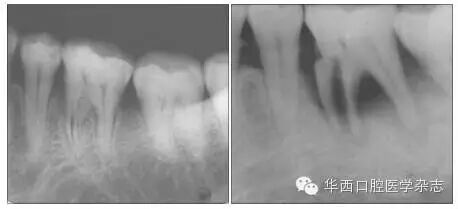

左:36牙近中根管下段内径增宽;右:36牙折线明显,折片向近中移位,伴牙槽骨吸收。

1 36牙近中根牙根折裂